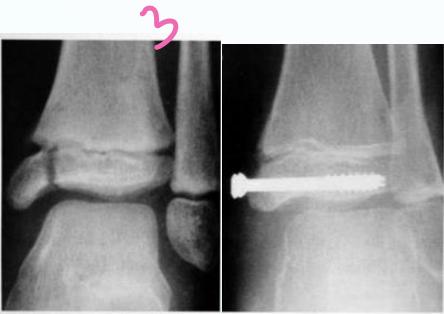

- Type I - Through the physis

- Type II - Through the physis with small piece of metaphysis (75%)

- Unstable: K-wire / screws with cast

Intra-articular (Type III / IV)

- Anatomical reduction and internal fixation